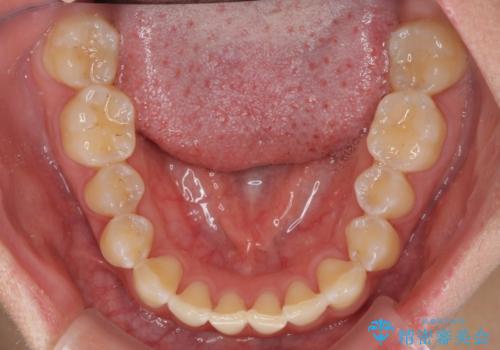

前歯の隙間と上下正中のズレを解消

- 上下前歯隙間と正中のズレを改善したいとのことで来院された患者様です。

正中がなかなか合わずに、2年近くの治療期間を要しました。